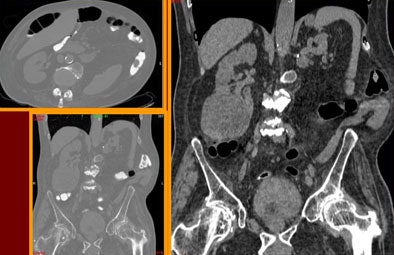

![]() |

| Above and below: Despite suboptimal distension, VC detected two significant polypoid lesions in the sigmoid colon of a 61-year-old paraplegic with fecal occult blood, following unsuccessful colonoscopy. The patient's parents had both died of colon cancer. Digital subtraction was used to detect the fluid-submerged polyps. |